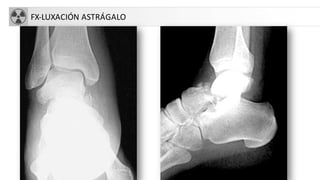

• Astrágalo (3% Fx pie)

• Segundo lugar en fracturas de tarso tras Fx

calcáneo.

• Mecanismo: hiperflexióndorsal pie.

• +Frecuente en cuello astragalino.

FX-LUXACIÓN ASTRÁGALO